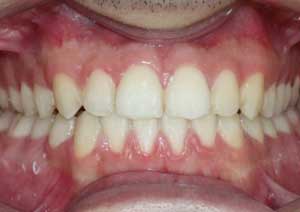

Traitement : Dans ce cas, nous avons eu recours à la mise en place de cales postérieures en résine bleue au niveau des premières molaires maxillaires, Elles ont permis de séparer temporairement les mâchoires afin de laisser les dents du haut se replacer correctement devant celles du bas, corrigeant ainsi le cross-bite antérieur.

Par la suite, ces cales ont été déplacées sur les faces palatines des incisives maxillaires dans le but d’optimiser l’articulé postérieur, notamment au niveau des molaires droites, qui présentaient également un articulé inversé.

Après